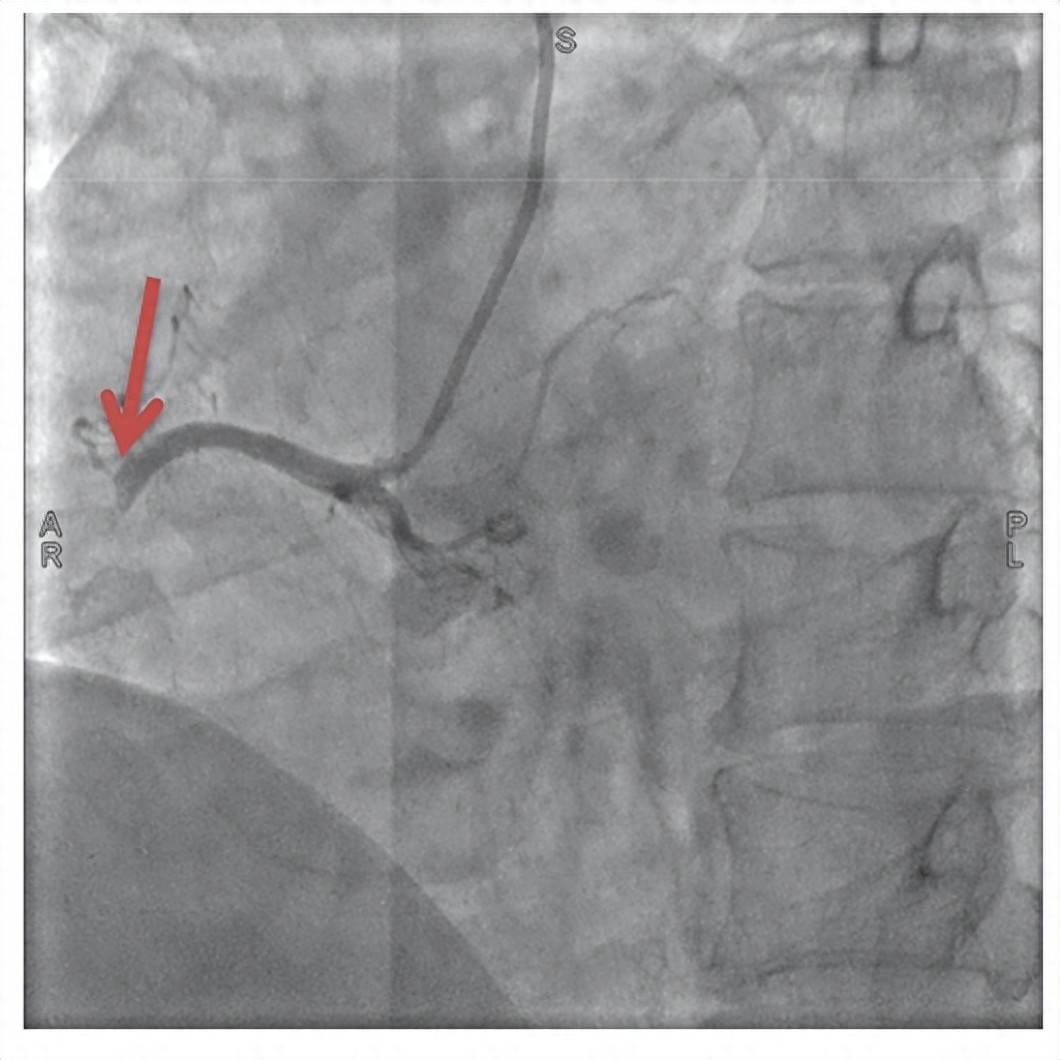

郑先生一入院,心电图检查瞬间锁定其为“急性下壁心肌梗死”,即因右冠状动脉或左回旋支急性闭塞导致的危急重症,随时可能引发恶性心律失常、心源性休克、猝死等致命风险。

闭塞的右冠状动脉

一场与时间的赛跑随即展开,泰康同济胸痛中心立即启动急性心肌梗死救治绿色通道,急诊冠状动脉造影显示郑先生右冠状动脉完全闭塞。从进入医院大门到手术器械成功开通堵塞血管仅用时51分钟,远低于国际公认的90分钟黄金标准。术后郑先生胸痛症状迅速缓解,生命体征逐渐平稳,目前已转入普通病房观察。